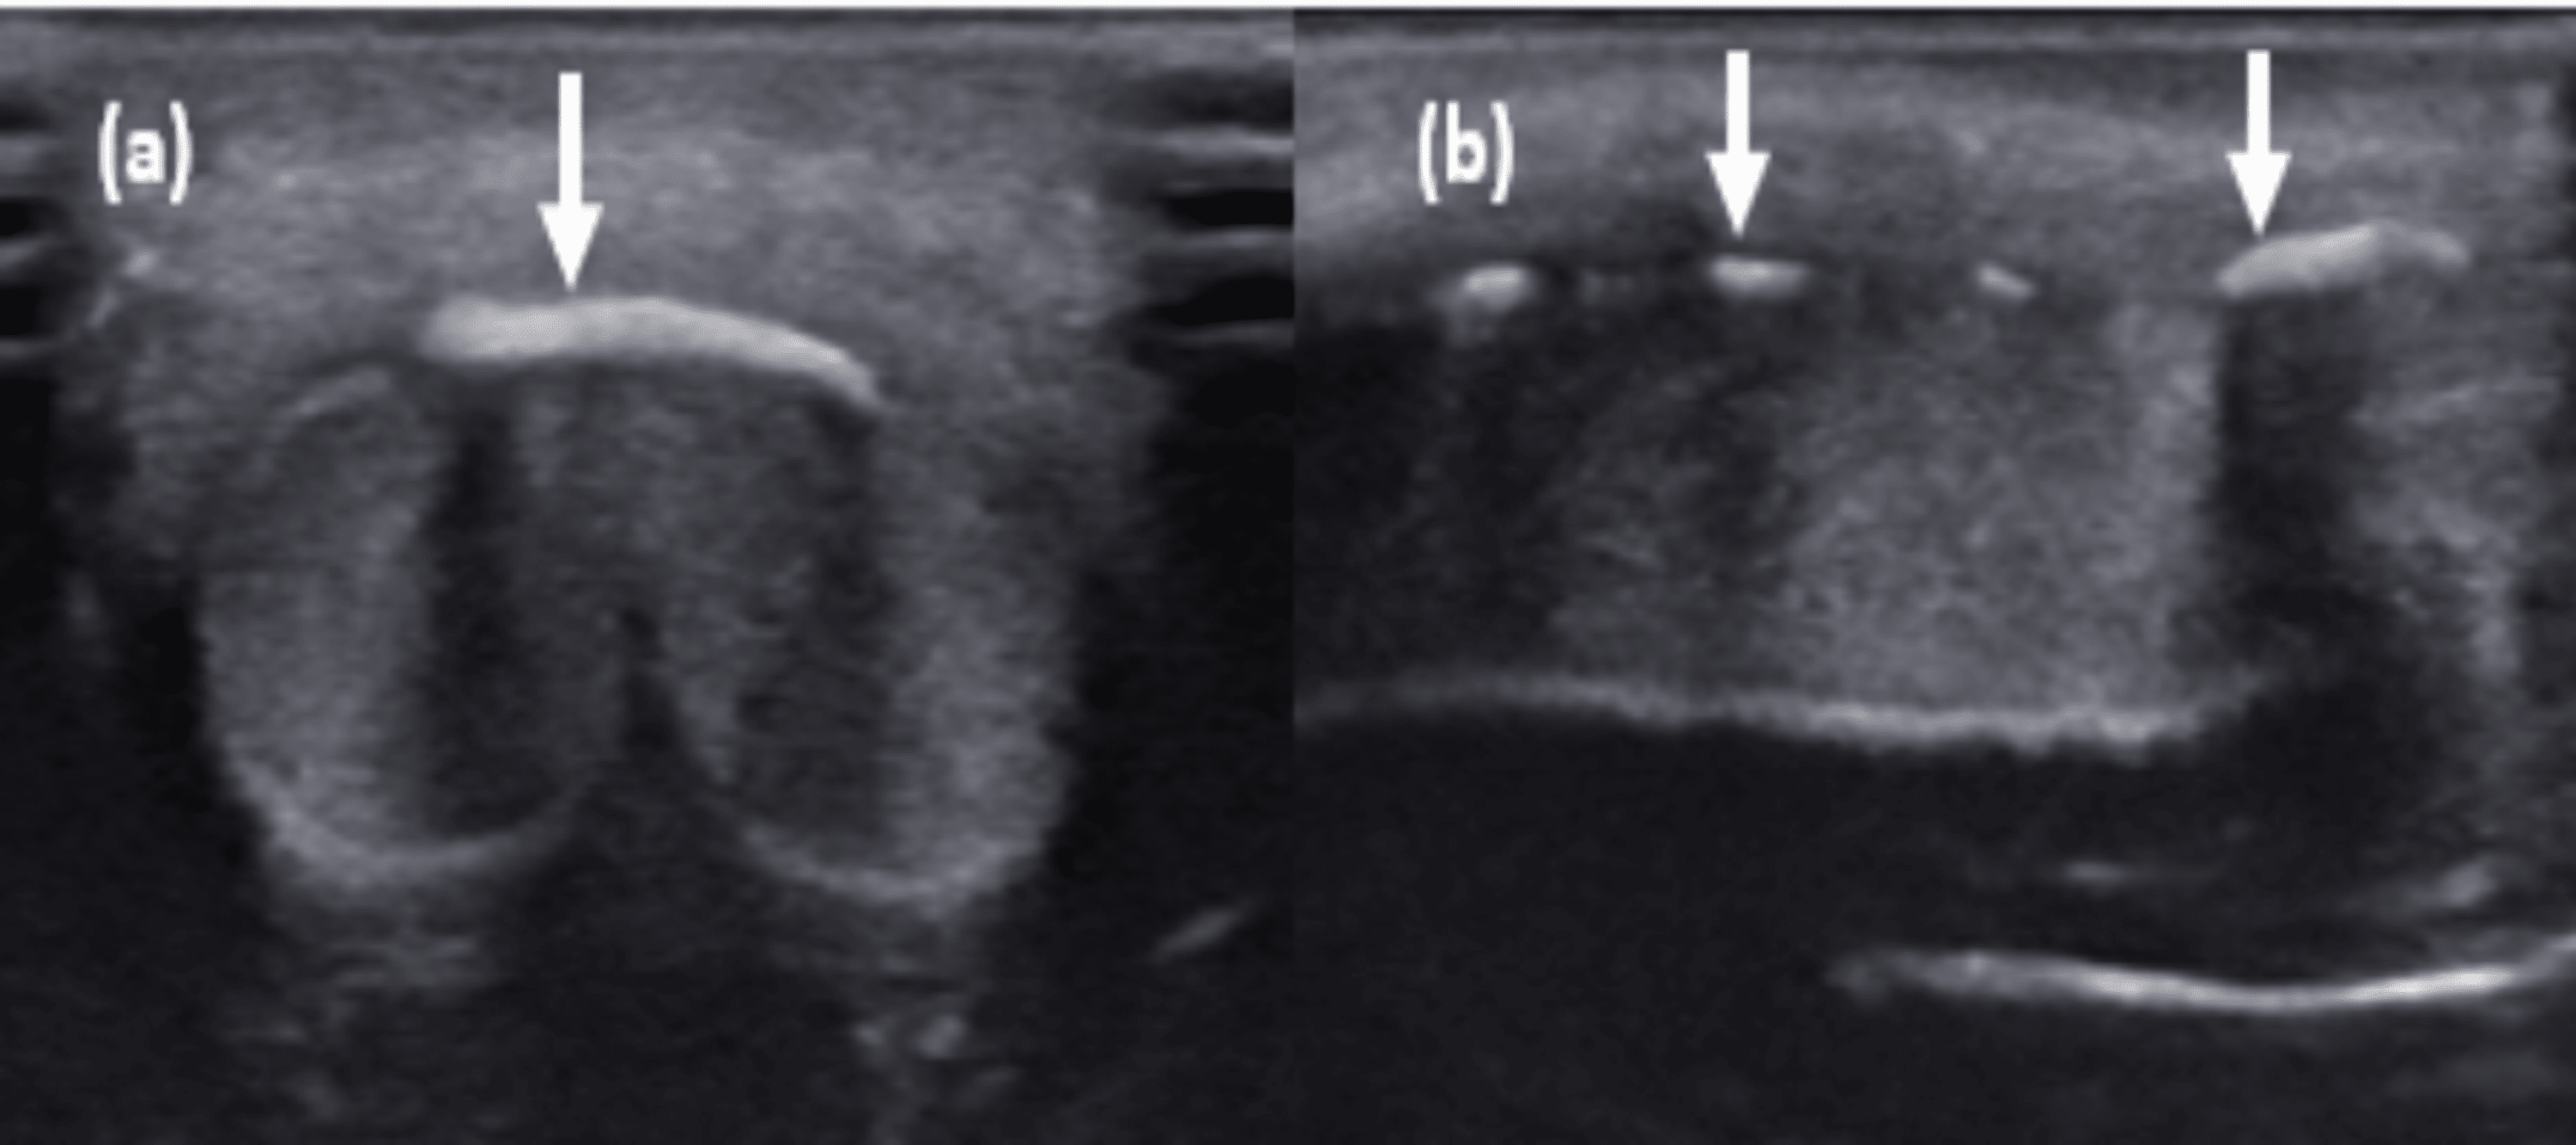

Radiographic images of a 10yearold male with Pyle disease. A, B Pyle Disease Radiology Flaring of femoral, tibial and fibular metaphyses. Pyle disease is a bone disorder characterized by knock knees (genu valgum), relative constriction of the diaphysis or shaft of the bone and flaring. Inward bowing of the tibias. Pyle's disease is an extremely rare skeletal disorder characterized by a benign. Metaphyseal dysplasia (pyle disease) is characterized by striking metaphyseal broadening of the. Pyle Disease Radiology.

Radiographic images of a 10yearold male with Pyle disease. A, B Pyle Disease Radiology Metaphyseal dysplasia (pyle disease) is characterized by striking metaphyseal broadening of the tubular bones [35, 36]. Pyle's disease is an extremely rare skeletal disorder characterized by a benign. Flaring of femoral, tibial and fibular metaphyses. Pyle disease is a rare genetic skeletal disorder which is conventionally classified with craniotubular dysplasias. Pyle disease is a bone disorder characterized by knock knees. Pyle Disease Radiology.